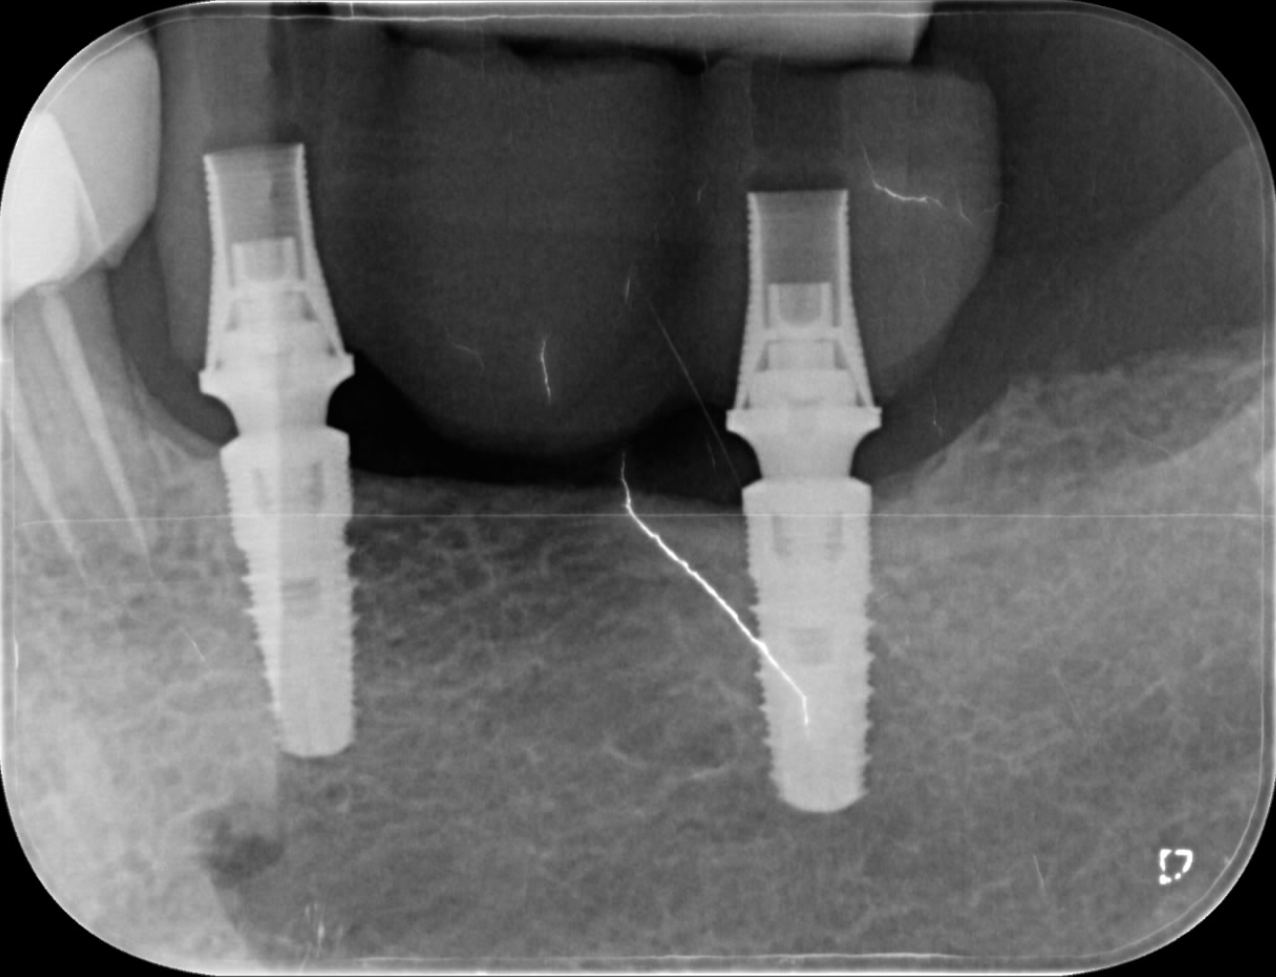

The use of intra-oral scanners to capture impressions has demonstrated high accuracy compared with conventional techniques.1, 2 The importance of ensuring a precise intra-oral scan is often under-estimated, and accurate intra-oral data capture is the true starting point for a successful restoration. Accurate transfer of the implant position is essential for achieving a perfect match between the digital design and clinical reality. Having an optimised geometry and being made of a highly readable scanning material, the ProCam scan bodies allowed the position of the implants and the profile of the peri-implant tissue to be captured with extreme fidelity (Fig. 3).

Fig. 3: Extreme fidelity of capture of the implant position and surrounding tissue profile using the ProCam scan bodies.